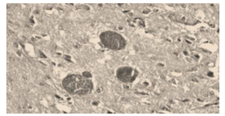

Na análise histopatológica abaixo, observam-se

cistos contendo estruturas arredondadas

compatíveis com protozoários. Esses parasitas

estão associados a zoonoses relevantes e podem

comprometer a qualidade sanitária de produtos de

origem animal.

Sobre o texto e a figura, analise as alternativas e assinale a CORRETA: